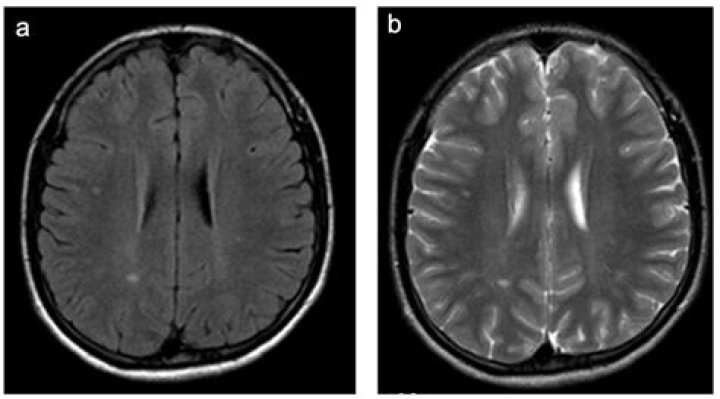

Leukoencephalopathy with vanishing white matter is a progressive disorder that mainly affects the brain and spinal cord (central nervous system). This disorder causes deterioration of the central nervous system’s white matter, which consists of nerve fibers covered by myelin.

Leukoencephalopathy (leukodystrophy-like diseases) is a term that describes all of the brain white matter diseases, whether their molecular cause is known or unknown. It can refer specifically to any of these diseases: Progressive multifocal leukoencephalopathy.